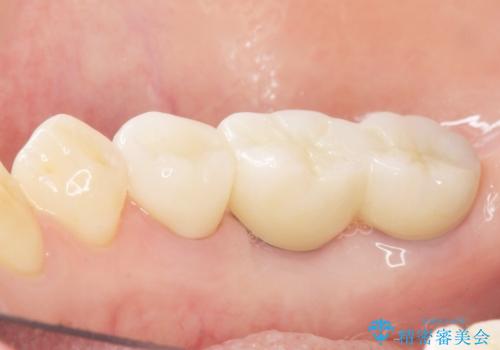

奥歯でしっかり噛むことができるようになり、喜んで頂けました。

セラミッククラウンの審美的な仕上がりにもご満足頂けました。

インプラントの種類:ストローマン BLT

クラウンの種類:ベレッツァクラウン(右下76)、ジルコニアクラウン スタンダード(右下5)